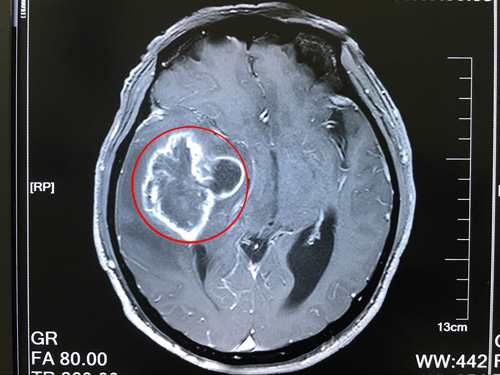

患者术前核磁影像:右侧颞叶占位,右侧高颅压,大脑镰疝

到院后,沈建康教授接待了薛老汉,看了他的影像资料,询问了病史病情后,安排他完善了相关检查。患者住院后,沈教授将患者的病情,手术预后、以及风险和家属做了沟通。他说:胶质瘤是恶性肿瘤,现在患者的胶质瘤已属于3-4级,非常高危,如果不及时做手术,后果将不堪设想。